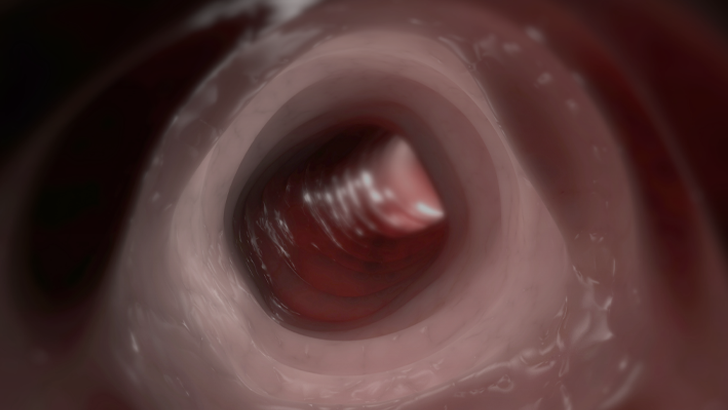

This is an area where we have provided updated recommendations compared to the prior iteration of the ACG guidelines in 2015. There is increasing data that patients who have severe hematochezia with active bleeding benefit from a CT angiogram because it’s been shown to be highly sensitive and specific in terms of detecting the location of bleeding. So we recommend that for patients who have severe hematochezia with active bleeding, those patients probably benefit from a CT angiogram as their initial diagnostic study as opposed to a rapid colonoscopy because those patients may not be able to tolerate a bowel preparation. And oftentimes, performing a colonoscopy is challenging with these patients because when we perform a colonoscopy, we may only see blood in the colon. So for those patients who have active bleeding and whom they have had a recent episode of hematochezia within, I’d say four to six hours of presentation, those patients likely benefit from an immediate CT angiogram.

The CT angiogram is noninvasive, it’s done without oral contrast, and it can rapidly detect the etiology and location of bleeding. And those patients who have a CT angiogram, which shows extravasation of contrast into the gut, they can then be triaged to interventional radiology where they can undergo an angiogram with embolization of bleeding. Another option is for patients who have positive CTA with extravasation, those patients may also benefit from performing a timely colonoscopy to then perform a therapeutic intervention. So I do think there’s an expanded role for CTA for patients with active lower GI bleeding.

Now the converse of that is there is limited role for a CTA in those patients in whom bleeding has subsided. So let’s say a patient has had some small volume bleeding or they haven’t had any bleeding in the last 12 hours. Those patients probably don’t need a CTA, and they would benefit from going to colonoscopy.